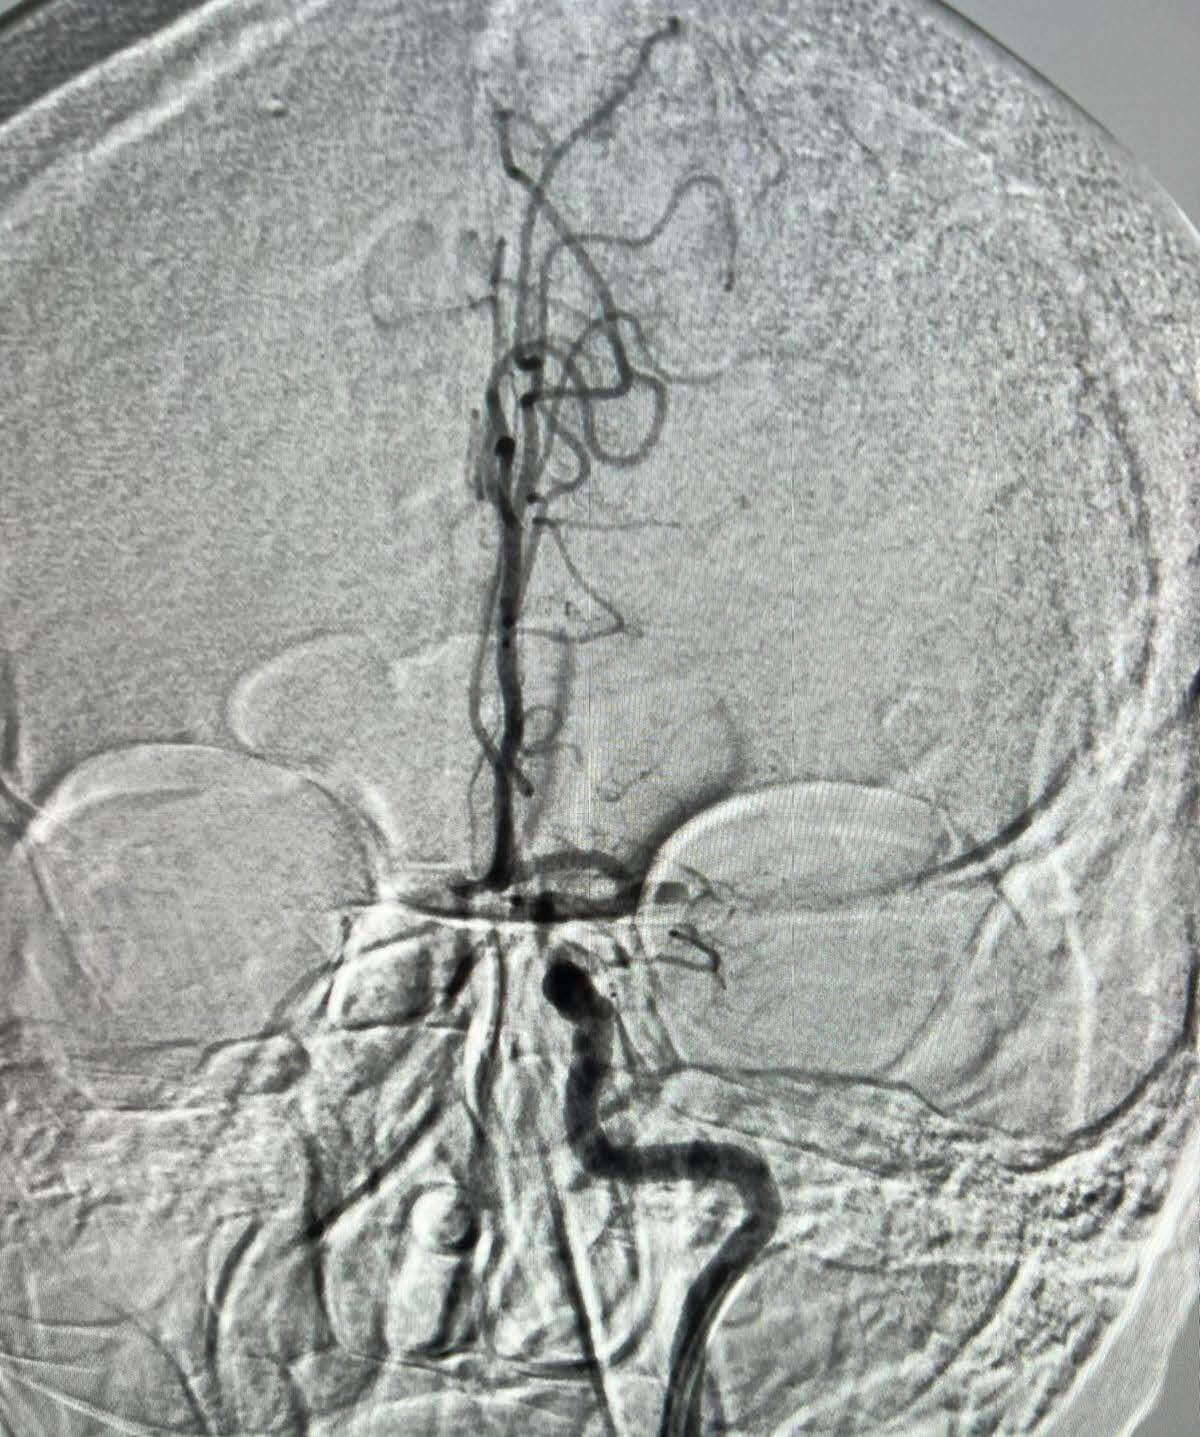

Спочатку пацієнтці виконали тромболізис – тобто внутрішньовенно ввели фермент, який розсмоктує тромби. Після цього частково відновилася мова, але рухи у правих руці та нозі не відновлювалися. Тому було прийнято рішення про виконання важливого втручання – механічної тромбектомії. Лікар Олександр Журавльов, який тільки на минулому тижні повернувся з навчань у м. Полтава з приводу механічної тромбектомії, блискуче виконав операцію. Він через стегнову артерію завів у судини голови тоненьку трубочку та пристрій, який зветься стент-ретривер. Останній – це виконана з тонюсенького дроту сітка, яка розкривається у просвіті судини, врізається у тромб та дістається разом з тромбом. Додатково використовувався аспіраційний катетер. Разом, шляхом витягування стент-ретриверу та аспірації катетером видалено тромб з середньої мозкової артерії.

Механічна тромбектомія — це мінімально інвазивна ендоваскулярна операція, яка проводиться для видалення тромбу з артерії. Хірург виконав цю складну процедуру, використовуючи найсучасніші технології. Через стегнову артерію було введено тонкий катетер, який провели до судин голови. За допомогою цього катетера лікар доставив до тромбу пристрій, що називається стент-ретривер. Ця спеціальна сітка, виготовлена з тонкого дроту, розкрилася всередині артерії, проникла в тромб і дозволила хірургу витягнути його разом із сіткою. Додатково для кращого видалення залишків тромбу був використаний аспіраційний катетер.